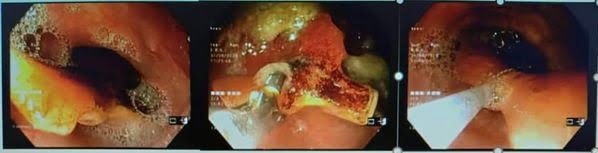

Ngày 31/8/2020 Bệnh viện đa khoa Sơn Tây đã làm thủ thuật lấy dị vật Răng giả rơi mắc ở thực quản thành công tại khoa Nội soi tiêu hóa- Bệnh viện đa khoa Sơn Tây thực hiện. Bệnh nhân Nguyễn Duy H 62 tuổi Trung Hưng- Sơn Tây đến bệnh viên ĐK Sơn Tây khám trong tình trạng mắc vướng khó chịu ở họng kèm ho kéo dài và điều trị không khỏi. Qua khám khai thác bệnh nhân cho biết sáng nay 31/8/2020 ăn cơm, uống thuốc thì bị rơi răng giả cảm giác nghẹn ở cổ khó chịu tím tái. Ngay sau đó bệnh nhân đến khám BV Sơn Tây nghi có dị vật đường tiêu hóa được các bác sỹ cho đi làm Nội soi Thực quản dạ dày… Kết quả Nội soi phát hiện có dị vật nằm ngang ở 1/2 Thực quản (dị vật có 3 cạnh) mắc vào thành TQ , thực quản sưng nề đỏ có điểm trợt loét do tình trạng viêm quá nghiêm trọng . Trước tình hình đó các Bác sỹ khoa Nội soi đã hội chẩn lãnh đạo bệnh viện & giải thích cho người nhà bệnh nhân là có dị vật mắc ở trong TQ cần lấy ra. Dưới sự chỉ đạo của đồng chí Giám đốc Ts Đặng Đức Hoàn các bác sĩ xác định đây không là 1 dị vật không đơn thuần (vì dị vật to có 3 cạnh), rất nguy hiểm và đòi hỏi phải được xử lý ngay nếu không sẽ để lại một số biến chứng nặng nề như chảy máu, tạo ổ áp xe, thủng trung thất hoặc đâm vào và làm tổn thương những động mạch có kích thước lớn xung quanh thực quản. Vậy cần phải gây mê cho bệnh nhân để đưa dụng cụ vào tiếp xúc dị vật đẩy xuôi xuống rồi dùng giỏ gắp ra. Sau khi tiến hành xong thủ thuật gắp ra là 1 răng giả có kt (2,5 x 2,5×1,5) cm bệnh nhân ổn đinh, vào viện điều trị bảo tồn vết thương sây sát họng- thực quản. Qua đây cho thấy mắc dị vật đường tiêu hóa như hóc xương, răng giả… hoặc hóc đồ ăn là tình trạng cấp cứu đường tiêu hóa nguy hiểm, có khả năng dẫn đến những biến chứng gây nguy hiểm cho tính mạng người bệnh. Vì vậy, để tránh dị vật đường tiêu hóa thì bệnh nhân cần có thói quen ăn uống khoa học, tránh để dị vật có cơ hội đi vào đường tiêu hóa và ngay khi có những triệu chứng nghi ngờ thì cần đến ngay cơ sở y tế để được phát hiện và có biện pháp điều trị nhanh nhất trước khi bệnh diễn biến nặng nề hơn. Nhưng đến với Bệnh viện ĐK Sơn Tây với đội ngũ bác sỹ điều dưỡng… vững về Y thuật, Tâm sáng trong & tập thể đoàn kết đồng lòng cùng chí hướng thì chắc chắn người dân trong khu vực sẽ được hưởng các dịch vụ kỹ thuật mới tiến bộ ngay tại bệnh viện Sơn Tây này mà không cần phải về bệnh viện trung ương.